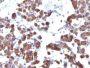

Thyroglobulin(TGB04 + TGB05), CF405S conjugate, 0.1mg/mL

Thyroglobulin is a 660 kDa dimeric pre-protein with mutiple glycosylation sites. It is produced by and processed within the thyroid gland to produce the hormone thyroxine and triiodothyronine. Prior to forming dimers, thyroglobulin monomers undergo conformational maturation in the endoplasmic reticulation. The vast majority of follicular carcinomas of the thyroid will give positive immunoreactivity for anti-thyroglobulin even though sometimes only focally. Poorly differentiated carcinomas of the thyroid are frequently anti-thyroglobulin negative. Adenocarcinomas of other-than-thyroid origin do not react with this antibody. This antibody is useful in identification of thyroid carcinoma of the papillary and follicular types. Presence of thyroglobulin in metastatic lesions establishes the thyroid origin of tumor. Anti-thyroglobulin, combined with anti-calcitonin, can identify medullary carcinomas of the thyroid. Furthermore, anti-thyroglobulin, combined with anti-TTF1, can be a reliable marker to differentiate between primary thyroid and lung neoplasms.Primary antibodies are available purified, or with a selection of fluorescent CF® Dyes and other labels. CF® Dyes offer exceptional brightness and photostability. Note: Conjugates of blue fluorescent dyes like CF®405S and CF®405M are not recommended for detecting low abundance targets, because blue dyes have lower fluorescence and can give higher non-specific background than other dye colors.

Positive Control

IHC, FFPE (verified)

Higher concentration may be required for direct detection using primary antibody conjugates than for indirect detection with secondary antibody|Immunohistology formalin-fixed 0.1-0.2 ug/mL|Staining of formalin-fixed tissues requires boiling tissue sections in 10 mM citrate buffer, pH 6.0, for 10-20 min followed by cooling at RT for 20 minutes|Flow Cytometry 0.5-1.0 ug/million cells in 0.1 mL|Optimal dilution for a specific application should be determined by user